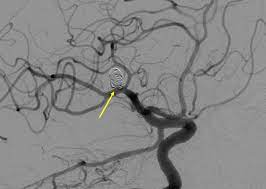

Kleines aneurysma im kopf. Ein Aneurysma vor allem im Gehirn kann angeboren sein. Häufig befinden sich die Aneurysmen im Kopf an den Aufzweigungen Bifurkationen der Arterien. Schließlich kann das Aneurysma platzen und eine unter Umständen lebensgefährliche Blutung im Kopf bewirken.

Ein Aneurysma vor allem im Gehirn kann angeboren sein. Da das Schiff beginnt sich aufzublähen wird es wahrscheinlicher zu platzen. Niemand kann vorhersagen wann ein Aneurysma platzt und Leck Blut in die umliegenden Gebiete. Solange ein Aneurysma noch klein und intakt ist das Gefäß also keine Risse hat verursacht es häufig keinerlei oder nur unspezifische Beschwerden wie Kopfschmerzen oder Übelkeit. Wenn ein Blutgefäß erweitert oder Ballons durch Schwächung Wände heißt es ein Aneurysma. Je nach Größe und Lage des Aneurysmas im Gehirn können jedoch auch Beschwerden auftreten. Ein Aneurysma ist eine krankhafte Aussackung einer Schlagader. Fachleute gehen aber davon aus dass Aneurysmen mit einem Durchmesser unter sieben Millimetern nicht sofort behandelt werden müssen sondern beobachtet werden können. Je nach Größe und Ort sind weitere Symptome möglich.

Nicht rupturierte intrakranielle Aneurysmen finden sich bei etwa drei Prozent der Erwachsenen. Ein Aneurysma ist eine krankhafte Gefäßausstülpung also eine örtlich begrenzte Erweiterung einer Arterie. Ein Aneurysma ist eine krankhafte Gefäßausstülpung die sich an den hirnversorgenden Gefäßen zumeist an Gefäßaufzweigungen befindet. Die meisten Gefäßaussackungen im Kopf entdecken Ärzte durch Zufall oder weil sie Symptome wie beispielsweise Doppeltsehen verursachen. Täglich im Kühlschrank aufbewahren. Aber es lässt sich nicht ganz ausschließen dass auch solche kleinen Aneurysmen reißen. Niemand kann vorhersagen wann ein Aneurysma platzt und Leck Blut in die umliegenden Gebiete.